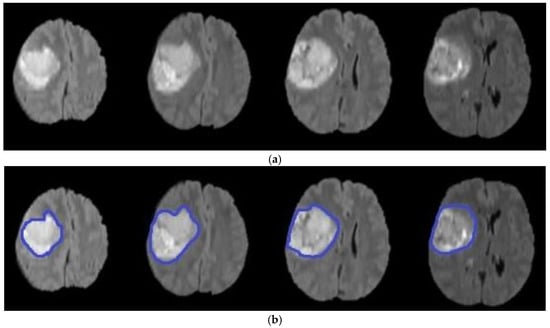

4.2. Experiment 2: Model Accuracy with and without k-Means

| Methods | Accuracy | Mean | Standard Deviation |

|---|---|---|---|

| k-means, DA and level set | 98.10 | 95.67 | 0.02 |

| DA, level set | 85.67 | 82.56 | 0.04 |